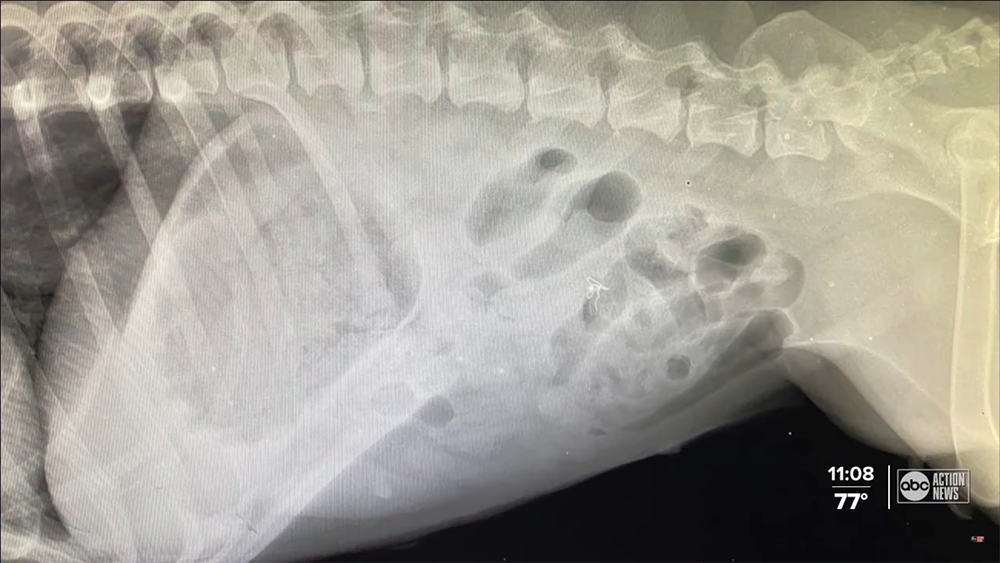

Lindsey suspected that Jada must have eaten something she shouldn’t have but didn’t know what. Jada was X-rayed at the HSTB hospital, and they confirmed that something was stuck at the bottom of her stomach. It turned out that Jada ate a drone.

The hospital immediately arranged for Jada to go through emergency surgery. “If Jada had not had surgery, I’d say 24-48 hours, there probably would have been a hole in the intestines, which would have led to an infection in the abdomen and would have had a very poor prognosis,” Dr. Justin Boorstein said.